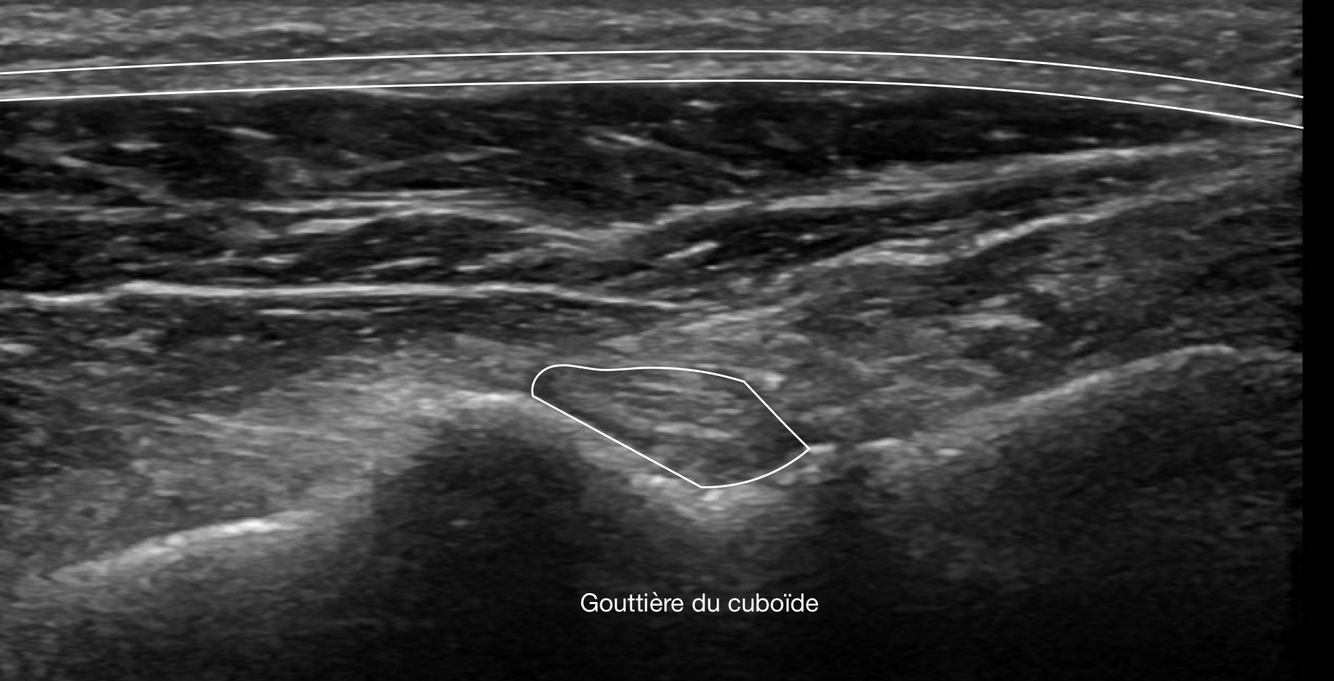

Q

Identifie le muscle long fibulaire sur l’image

Dans quelle structure ce muscle passe-t-il?

A

How well did you know this?